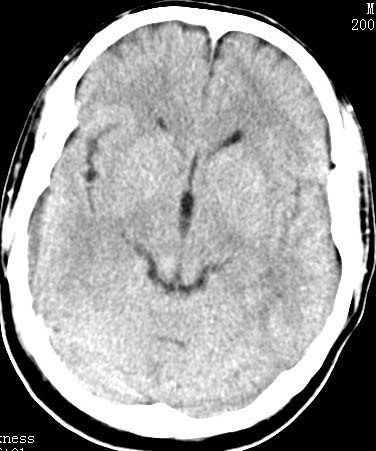

以下是引用clj20在2007-8-29 9:47:00的发言:[br]蛛网膜下腔出血,左侧额叶不均匀密度影,占位效应明显,界限不清。支持:占位性病变,建议增强!

以下是引用xulianj在2007-8-29 20:15:00的发言:[br]蛛网膜下腔出血,左侧额叶不均匀密度影,占位效应明显,界限不清。支持:占位性病变,建议增强!

以下是引用jiangjing在2007-8-29 14:33:00的发言:[br]左侧额叶不均匀密度影[低密度为主,边缘见等密度环环绕]占位效应明显,界限不清。支持:占位性病变,建议增强! [br][br]